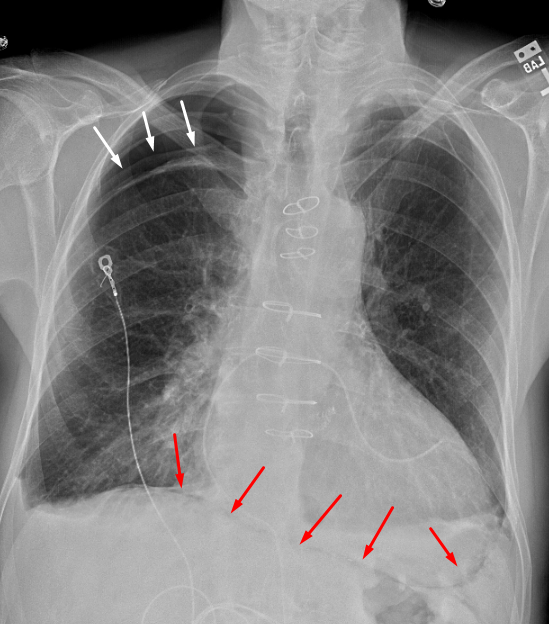

Age: 66

Sex: Male

Indication: Post-op ascending aortic aneurysm repair

Sample ReportModerate-sized right apical pneumothorax. No mediastinal shift.

Pneumomediastinum tracking along the pericardium and extending into the anterior mediastinum.

Small bilateral pleural effusions.

Hazy bibasilar opacities likely represent atelectasis in this postoperative patient.